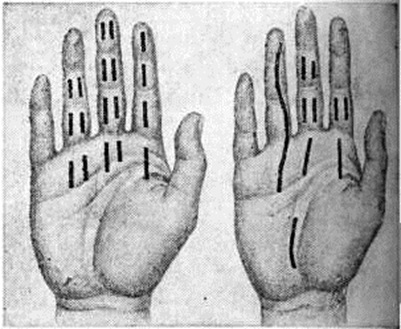

ПанарицийПанариций (латынь panaricium) острое воспаление тканей пальца, возникающее обычно в результате инфицирования мелких его повреждений. Воспалительные процессы, осложняющие обширные ранения пальцев, не относятся к Панариций В этих случали говорят об инфицированных ранах пальцев. Классификация. Для практической работы хирургов наиболее целесообразна классификация Панариций, основанная на учёте анатомической локализации воспалительного процесса (рисунок 1). По этой классификации различают следующие виды Панариций: кожный, околоногтевой (паронихия), подногтевой, подкожный, костный, суставной, сухожильный, пандактилит. Статистика. Чаще Панариций болеют лица, выполняющие работу, связанную с возможностью травмирования рук, загрязнением их смазочными материалами, раздражающими кожу веществами (разнорабочие, грузчики, слесари, трактористы, рабочие ткацкой промышленности и другие). У 80% заболевших наблюдается Панариций ногтевых фаланг I, II или III пальцев правой кисти. Этиология и патогенез. Наиболее распространённым возбудителем Панариций является белый или золотистый гемолитический стафилококк в монокультуре или в ассоциации с другими микробами. Реже воспаление обусловливается кишечной палочкой, протеем, стрептококком и другие. Иногда причиной заболевания служит гнилостная, а также грибковая инфекция. Микробы проникают в ткани из окружающей среды или поверхностных слоёв кожи пальца при мелких, особенно не санированных повреждениях (ссадины, раны, нанесённые острыми предметами иголками, металлическими стружками, деревянными занозами и другие); крайне редко инфицирование происходит гематогенным путём. Возникновению Панариций способствуют снижение иммунологический реактивности организма, истощение, нарушение обмена веществ, эндокринные заболевания, а также длительное воздействие на кожу рук раздражающих веществ, холода, влаги, вибрации, при которых наступают расстройства микроциркуляции и трофики тканей, нарушается защитная функция кожи. Экспериментально доказано, что многие химический вещества и металлы (медь, цинк, кобальт, хром и другие), попадая в рану, оказывают на ткани токсическое действие и также способствуют возникновению Панариций Дальнейшее развитие и особенности течения Панариций в отличие от гнойных заболеваний других локализаций в значительной мере определяются особенностями анатомического строения пальца: обилием на небольшом протяжении функционально важных образований (фиброзные влагалища, сухожилия, синовиальные влагалища, сосуды, элементы, образующие суставы), ячеистостью расположения подкожной клетчатки, пронизанной фиброзными перемычками. Все эти факторы способствуют проникновению инфекции вглубь и переходу её на сухожилия и костносуставной аппарат. Фаза серозного пропитывания тканей обычно короткая, быстро сменяется фазой гнойно-некротического воспаления, так как скопление экссудата в замкнутых пространствах приводит в короткие сроки к нарушению кровообращения, некрозу тканей, гнойному их расплавлению. Клиническая картина. Постоянным признаком всех форм Панариций является сильная боль пульсирующего характера, резче выраженная в центре гнойного очага и при локализации его на ладонной поверхности пальца, где ткани неподатливы и обильно снабжены нервными окончаниями. Боль усиливается при движениях пальца, находящегося обычно в полусогнутом положении. Как правило, имеются выраженные в разной мере припухлость и отёчность пальца, гиперемия кожи, наиболее чётко определяющиеся на тыльной его поверхности, местное повышение температуры. Общие нарушения в организме больных выражены меньше, чем местные. В стадии нагноения боль становится мучительной, приводит к бессоннице; яркая краснота отмечается больше на периферии очага, чем в центре; температура тела повышена (с ремиссиями); определяются увеличение и болезненность регионарных лимфатических, узлов. При кожном Панариций гнойный очаг располагается в толще кожи (рис.< 1, 1) под эпидермисом. Образуется импетигиозный пузырь с серозным, гнойным или геморрагическим содержимым, который может располагаться как на ладонной, так и на тыльной поверхности любой из фаланг, иногда занимая почти всю поверхность пальца. |

Пузырь окружён узким воспалительным валиком. Боль вначале незначительная, но по мере накопления гноя усиливается, становится постоянной, пульсирующей. Иногда очаг гиперемии вокруг пузыря расширяется, присоединяется лимфангиит (смотри полный свод знаний) и регионарный лимфаденит (смотри полный свод знаний), сопровождающийся повышением температуры тела до высоких цифр. Ранее подобное поражение называли лимфатическим панарицием. В современной хирургической литературе этот термин практически не употребляется. При кожном Панариций гнойный очаг в толще кожи может сообщаться с очагом в подкожной клетчатке — так называемый панариций в форме запонки (рисунок 1, 8).

При околоногтевом Панариций— паронихии (смотри полный свод знаний) гнойное воспаление локализуется в толще валика ногтя: в боковом его участке, над корнем ногтя, или на всем протяжении валика (рисунок 1, 2). Кожа валика краснеет, припухает (цветной рисунок 1), из-под валика при надавливании появляются капли гноя.

Подногтевой Панариций характеризуется скоплением гноя под телом ногтя (рисунок 1,5). Он возникает при инфицировании проникающих под ноготь колотых ран, нагноении подногтевых гематом или как осложнение паронихии; протекает остро. Ноготь приподнят, сквозь него просвечивает гной. Ограничение гнойного очага плотной ногтевой пластинкой обусловливает постоянную резко выраженную пульсирующую боль.

Подкожный Панариций— воспаление подкожной клетчатки пальца (рисунок 1, 4) — наиболее распространённая форма Панариций Чаще встречается подкожный Панариций ладонной поверхности дистальных фаланг. Так как на тыльной поверхности пальцев кожа подвижная, а подкожная клетчатка рыхлая и содержит много лимфатических, сосудов, широко анастомозирующих с лимфатических, сосудами ладонной поверхности, то при расположении гнойного очага на ладонной поверхности пальца отёк, припухлость и гиперемия кожи более чётко выражены на боковых поверхностях и тыле пальца. Палец (или фаланга) увеличивается в объёме, становится напряжённым (цветной рисунок 2, 3). Большая толщина, плотность и неподатливость кожи ладонной поверхности, ячеистое расположение подкожной клетчатки способствуют быстрому распространению воспалительного процесса в сторону надкостницы и сухожилий. Боль постоянная, усиливается при разгибании и ослабевает при умеренном сгибании пальца. Точка наибольшей болезненности соответствует локализации центра гнойного очага. Часто больной лишается сна из-за боли, изнурён, температура тела повышается до 38—39°. В гнойное воспаление могут вовлекаться кость, сухожилия, суставы (рисунок 2). Из очага, локализующегося в проксимальной фаланге пальца, гнойный процесс может перейти по рыхлой клетчатке межпальцевых промежутков в каналы червеобразных мышц, дистальный отдел ладони и на проксимальные фаланги соседних пальцев (рисунок 3).

Костным Панариций называется гнойное воспаление пальца с вовлечением в процесс костной ткани (рисунок 1, 5). Различают костный Панариций дистальной, средней и проксимальной фаланг. Костный Панариций может быть первичным, возникающим в результате глубоких колотых ран и заноса инфекции в кость ранящим предметом. Эта форма встречается редко. Преобладает вторичный костный Панариций, причина которого — переход воспаления с мягких тканей на кость. Некроз и гнойное расплавление обусловливают возникновение дефекта кости или образование секвестров. Клинические, картина костного Панариций в ранней стадии не отличается от таковой при подкожном Панариций Вскоре все симптомы становятся резко выраженными. При поражении дистальной фаланги палец приобретает колбообразную форму с напряжённой, блестящей, гладкой кожей. Боль носит постоянный характер. Появляется озноб, головная боль, температура повышается до 39° и выше. В гнойный процесс могут вовлекаться сухожилия, суставы.

Суставной Панариций характеризуется гнойным воспалением межфаланговых или пястно-фаланговых суставов (рисунок 1, 6). Различают две стадии течения суставного Панариций В I стадии в процесс вовлекаются только мягкие ткани сустава: появляется гиперемия кожи, отёк, сглаженность межфаланговых складок; палец приобретает веретенообразную форму. Толчкообразное давление по продольной оси пальца резко усиливает постоянную боль. При пункции сустава (смотри полный свод знаний: Суставы) можно получить мутную жидкость. Во II стадии разрушаются суставные хрящи, боковые связки, наступает деструкция костей, образующих сустав. Возникает патологический подвижность, вплоть до подвывиха в суставе, определяется крепитация суставных поверхностей. Может произойти самопроизвольное вскрытие такого Панариций, при этом образуется свищ с грануляциями и гнойным отделяемым.

Сухожильный Панариций— гнойное воспаление влагалища сухожилия и сухожилия пальца (рисунок 1, 7). Воспаления сухожилий разгибателей пальцев, как правило, не бывает. Сухожилия сгибателей пальцев обычно вовлекаются в процесс вторично, воспаление переходит на них с влагалища сухожилий. Сдавление тонких сосудов, подходящих к сухожилию через мезотендиний, быстро накапливающимся во влагалище сухожилия экссудатом и тромбоз их приводят в короткие сроки к некрозу сухожилия. Гной из влагалища может прорваться наружу с образованием свища (рисунок 4). При сухожильном панариции I пальца гной может распространяться по влагалищу сухожилия длинного сгибателя большого пальца кисти в общее синовиальное влагалище сгибателей и к V пальцу. Возникает так называемый перекрёстный панариций. Возможно распространение гнойного процесса и в обратном направлении — от V пальца к I. Иногда процесс может перейти на глубокие слои предплечья — в так называемый пространство Пирогова—Парона. Этого не наблюдается при сухожильном панариции II, III и IV пальцев, влагалища сухожилий которых изолированы от общего синовиального влагалища сгибателей кисти. Основной признак сухожильного Панариций—постоянная боль по ходу сухожилия, усиливающаяся при попытке разгибания пальца. Несвоевременное хирургическое вмешательство влечёт за собой некроз сухожилия на большом протяжении, отторжение которого происходит очень медленно. Нежизнеспособное сухожилие выглядит серым, тусклым. Сгибательная функция пальца выпадает.

Пандактилит (греческий pan всё + daktylos палец + -itis) — прогрессирующее гнойное воспаление всех тканей пальца, в том числе связок, сухожилий, костей и суставов. Возникает в результате осложнения или неправильного лечения более лёгких форм Панариций Палец резко деформируется, увеличивается в объёме, кожа приобретает багрово-цианотичный оттенок, напряжена, блестит. Имеются свищи, из которых выделяется гной, отторгаются участки некротизированной жировой клетчатки, сухожилий, костные секвестры; нередко наблюдается патологический подвижность и крепитация в межфаланговых суставах.